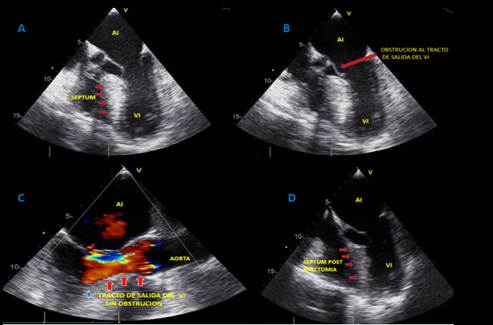

El ecocardiograma transtorácico mostró MCH septal con función sistólica preservada (fracción de eyección del ventrículo izquierdo -FEVI- 68%), disfunción diastólica tipo 2 con incremento en las presiones de llenado, severa dilatación auricular izquierda, esclerosis válvula mitral e insuficiencia leve a moderada; gradiente dinámico obstructivo hacia el tracto de salida del ventrículo izquierdo de 51 mmHg; esclerosis valvular aórtica con mínima insuficiencia, ventrículo derecho sin alteraciones y dispositivo en cavidades derechas bien posicionado (figura 2).

Figura 2. A-B-C:  Ecocardiograma transtorácico, en imágenes multidimensionales donde se evidencia clara hipertrofia septal evaluada en vista de eje largo y de 5 cámaras. D: Rx de tórax que confirma presencia de electrodos de cardiodesfibrilador. E: Tomografía de tórax que muestra severa hipertrofia septal con reducción de volumen ventricular izquierdo.

Figura 3. A-B:  Ecocardiograma transesofágico, en imágenes multidimensionales donde se evidencia hipertrofia septal en vista de esófago medio con obstrucción al tracto de salida y presencia de SAM (movimiento anterior septal de válvula mitral). C: Posoperatorio de miectomía septal que demuestra liberación de la obstrucción del tracto de salida del ventrículo izquierdo. D: Vista de corrección de hipertrofia septal con reducción septal ventricular izquierdo.